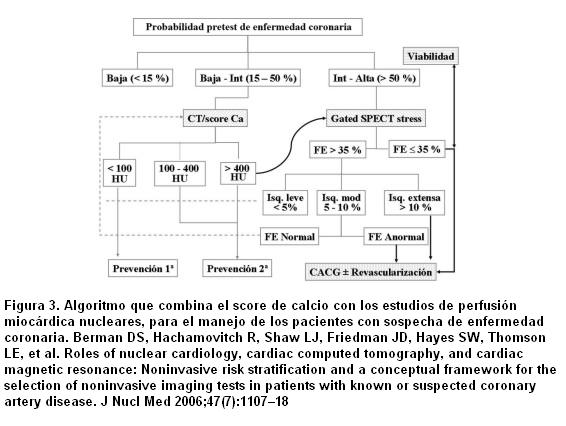

¿Cómo combinar los resultados de CCS y la SPECT (figura 3)? Varios estudios han comparado el CSS con los parámetros fisiológicos usados en los EPM (37-40). Estos reportes han proporcionado consistentes datos de que existe una relación lineal entre el CCS y las anormalidades en los EPM. En los pacientes con un CCS < 100 la tasa de eventos cardíacos es muy baja, lo que es coincidente con estudios angiográficos que muestran una baja probabilidad de EC significativa y una extremadamente baja probabilidad de incidencia de isquemia inducida en los estudios funcionales de estrés (promedio 2%), en este grupo de pacientes. Estos datos indican que los pacientes con un CCS < 100 no se benefician de un estudio de perfusión miocárdica. Han sido propuestas estrategias que utilizan un CCS umbral de > 400 para realizar los estudios de SPECT (37-39), basándose en que los pacientes con un alto CCS tienen una probabilidad intermedia de tener isquemia miocárdica silente. He y colaboradores (37) mostraron que los severos defectos de perfusión están confinados a los pacientes que tenían un CCS ³ 400. En el estudios de Berman y colaboradores (39), tres cuartas partes de los pacientes con isquemia tuvieron un CCS ³ 400. Estos resultados indican además que la probabilidad de detectar isquemia miocárdica mediante SPECT está fuertemente relacionada con el valor del CCS, esperándose que uno de cada tres o cuatro individuos con CCS ³ 400 tengan isquemia silente. Es notable que aproximadamente solo 10% de paciente sometidos a TC tienen un CCS ³ 400, lo que indica que solo una pequeña proporción requerirían EPM y que la probabilidad de encontrar un CCS alto con un SPECT normal es bastante rara. La evidencia actual sugiere que la estrategia de combinar el CCS y SPECT es más efectiva que la SPECT sola, para definir la necesidad de una terapia médica más agresiva (9).

Sin embargo aún se requiere mayor investigación, ya que entre los pacientes con EPM normal, existe un amplio rango de CCS (22% tenían CCS menor de 100, 56% tuvieron un CCS ³ 100 y 31% ³ 400) (39). Schepis y colaboradores (41) descubrieron que un CCS ³ 709 podría ser un valor de corte (cutoff) óptimo para detectar pacientes con EC obstructiva aun en presencia de EPM normales, lo que probablemente refleja “isquemia balanceada”. Con este umbral la combinación del CCS y los EPM mejoraría la sensibilidad para diagnosticar EC obstructiva sin una disminución significativa de la especificidad. Por el contrario, el CCS < 400 en pacientes sintomáticos y con probabilidad intermedia de EC puede ser menos efectivo para excluir la enfermedad, especialmente en sujetos jóvenes y mujeres. Schenker y colaboradores (42) estudiaron 621 pacientes con PET stress y CCS en el mismo procedimiento, su análisis de riesgo demostró un incremento de eventos mayores en los niveles de CCS altos, independientemente del grado de anormalidad en la perfusión. En efecto, la tasa anualizada de eventos en pacientes con PET de perfusión normal y CCS normal fue sustancialmente más baja que entre los que tenían un PET normal con un CCS ³ 1.000. Lo mismo sucedió con la tasa de eventos por año entre los pacientes con isquemia demostrada por la PET y CCS normal y los que tuvieron isquemia con un CCS ³ 1.000. Estos hallazgos sugieren que el añadir la información anatómica de la extensión de la aterosclerosis a los métodos nucleares convencionales suma información adicional en la estratificación del riesgo, pudiendo personalizar mejor las metas terapéuticas.